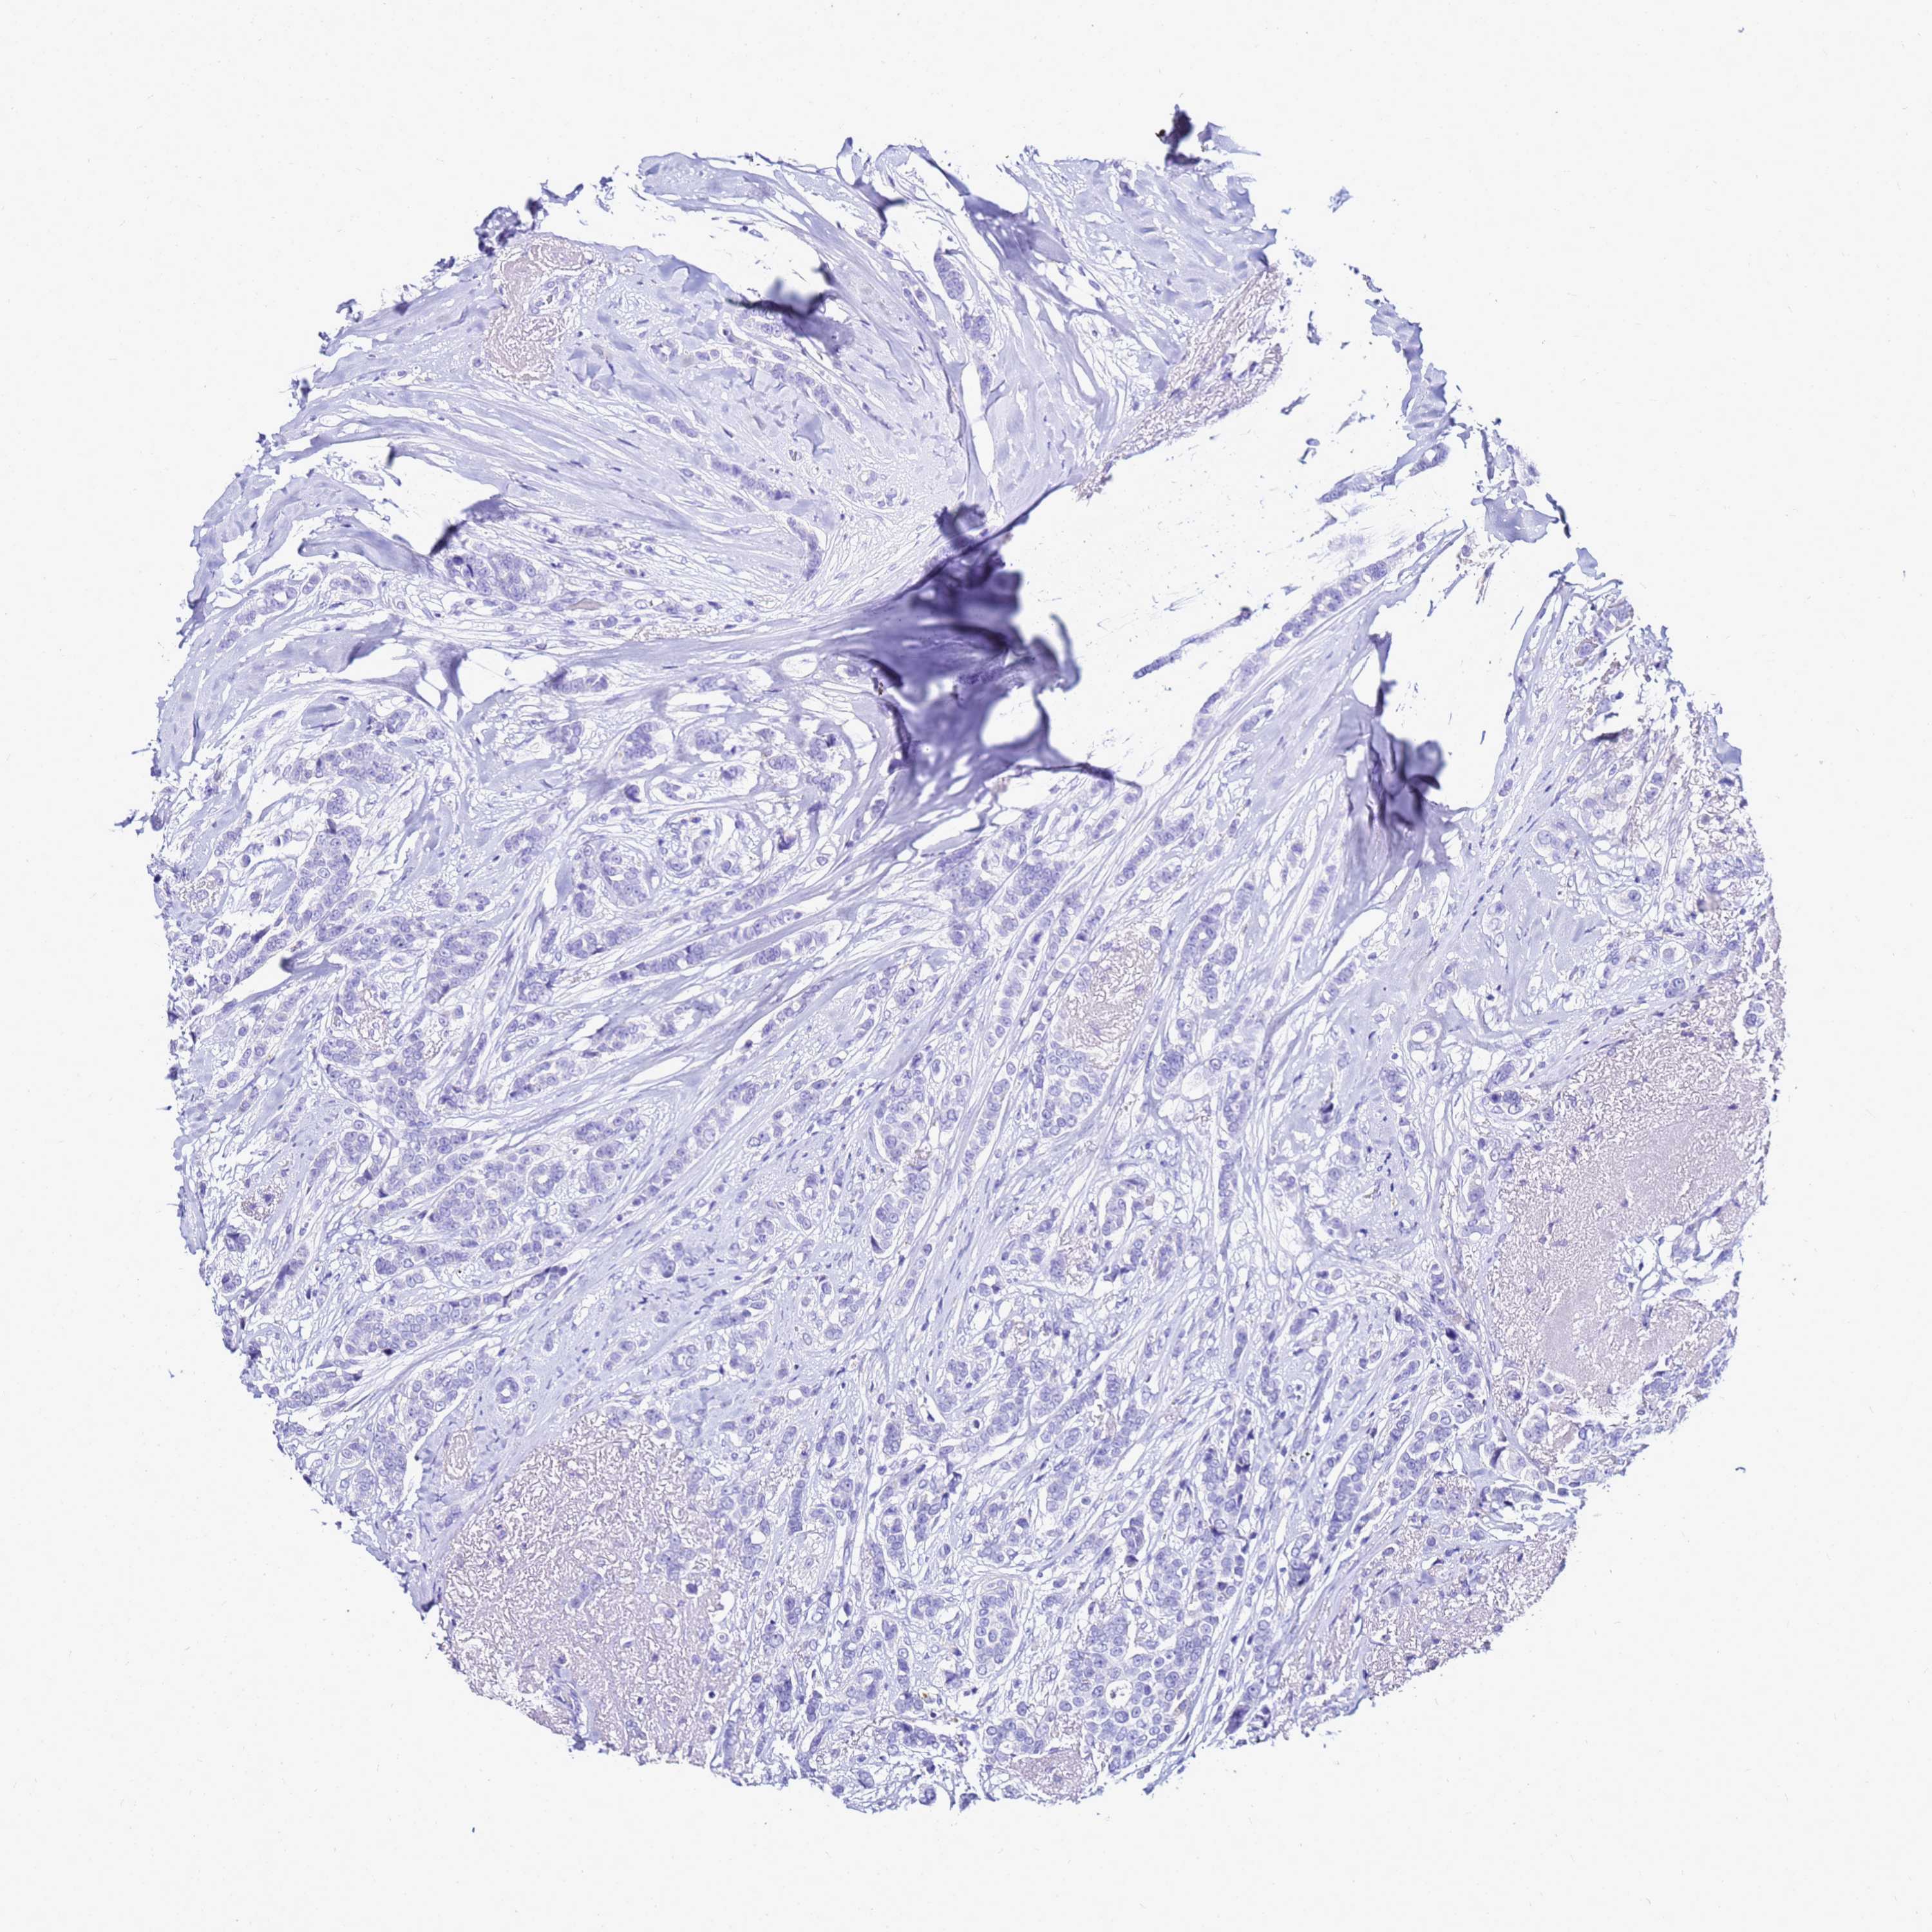

CANCER BREAST CANCER Show tissue menu

Breast cancer

Human cancer